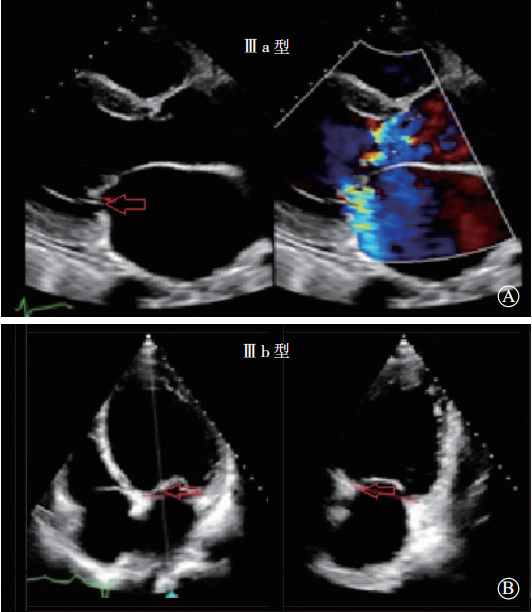

Ⅲ型:瓣叶活动受限的瓣膜功能异常(图4)。在Ⅲ型功能失调中,Ⅲa类指一个或多个瓣叶的运动在瓣叶开放或关闭时受到限制导致不同程度的狭窄或反流(瓣膜及瓣下组织增厚或钙化);Ⅲb类指一个或多个瓣叶的运动在瓣叶关闭时受到限制导致的反流(此类病变多为缺血性导致)。

图4 Ⅲ型,限制瓣膜运动 A. Ⅲa 型,瓣叶开放和关闭时均受到限制导致二尖瓣狭窄和反流;B. Ⅲ b 型,瓣叶关闭时受到限制导致二尖瓣反流